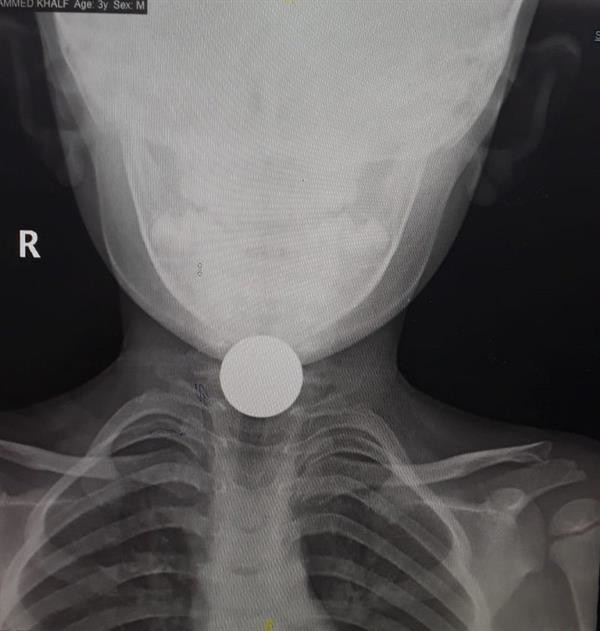

طائف: بچے کے حلق میں پھنسا سکہ نکال لیا گیا

والدین کم سن بچوں کی خصوصی نگرانی کریں(فوٹو، اخبار 24 )

طائف کے شاہ فیصل ہسپتال میں چار سالہ بچے کے حلق میں پھنس جانے والے سکے کو کامیاب آپریشن کے ذریعے نکال دیا گیا۔ بچے کو انتہائی نازک حالت میں ہسپتال پہنچایا گیاتھا۔

بچے کو سانس لینے میں شدید شواری کا سامنا کرنا پڑرہا تھا۔ والدین کا خیال تھا کہ اس نے کوئی چیز نگل لی ہے۔ ڈیوٹی پر موجود ڈاکٹرنے فوری طور پر بچے کا ایکسرے کرایا تو معلوم ہوا کہ حلق میں سکہ پھنسا ہوا ہے جسے بعدازاں آپریشن کے ذریعے نکال لیا گیا۔